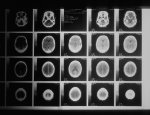

Расположение опухоли в организме влияет на тип симптомов, которые испытывает человек. Из-за сложности мозга и того факта, что он выполняет различные важные функции, любой рост органа может вызвать широкий спектр побочных эффектов.

"Есть один симптом опухоли головного мозга, которая может появиться во время еды. Он также может указать, в какой части мозга расположена опухоль. Хотя это редко, потеря вкуса и обоняния может быть связана с опухолями головного мозга в определенных частях мозга. Потеря вкуса и обоняния — это то, что можно легко заметить во время еды", - говорит врач-онколог Андрей Воробьев специально для МедикФорум.

Опухоль головного мозга в лобной доле может привести к потере обоняния (а также к другим симптомам, таким как трудности с речью, концентрацией внимания или изучением новой информации).

«Опухоль головного мозга в теменной доле может привести к затруднению сбора информации от ваших органов чувств, включая обоняние и вкус (а также к другим симптомам, таким как трудности с распознаванием лиц или объектов и координацией движений)».

Обонятельная нейробластома — опухоль в полости носа — может повлиять на обоняние. Она также может вызвать кровотечение из носа, привести к слезотечению и другим симптомам.